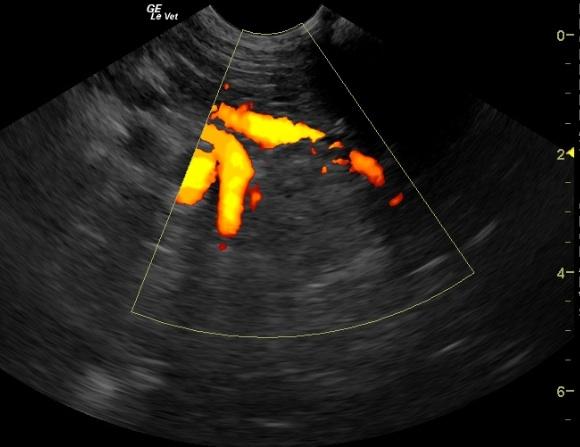

A 9 year old FS Labrador was presented for anorexia. Previous laboratory work had shown an inappropriate urine SG, 3+ proteinuria, microalbuminuria, azotemia, thrombocytosis, and negative 4Dx. The only significant abnormality on physical examination was dehydration. Baseline androstenedione and estradiol were elevated and ACTH stimulation revealed elevated cortisol, elevated estradiol, and elevated progesterone.